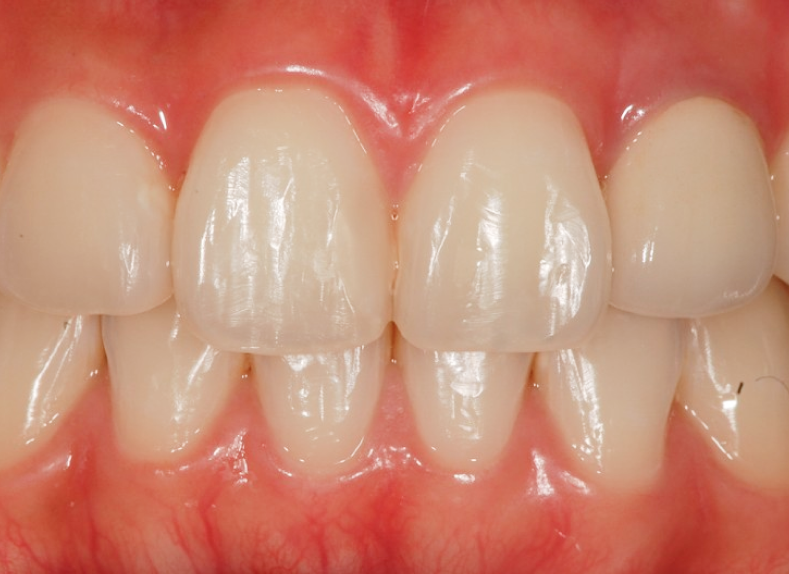

내원 당시 모습:

색이 변한 앞니 + 엑스레이에서 보인 문제

환자분은 거울에 비치는 앞니 색이

유독 한쪽만

회색빛으로 짙게 변해 보인다는 이유로

내원하셨습니다.

구강 내에서 확인했을 때도

다른 치아와 비교해

명확한 변색이 있었고,

단순 표면 얼룩과는 다른 양상이었습니다.